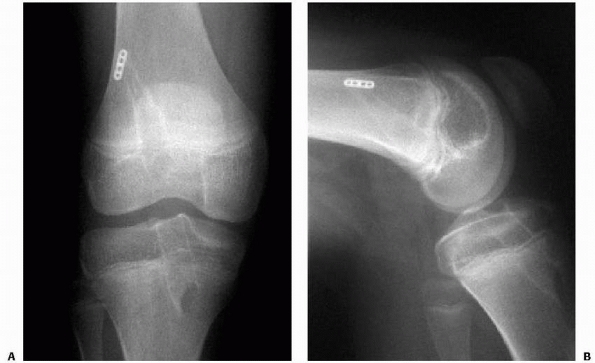

obtained to evaluate maintainance of reduction and fracture healing (Fig. 24-10).

![]() |

|

FIGURE 24-10

Type III tibial spine fracture in an 11-year-old male child treated with arthroscopic reduction and 3.5-mm cannulated screw fixation. Preoperative anteroposterior (A) and lateral (B) radiographs. Postoperative anteroposterior (C) and lateral (D) radiographs. |

of tibial spine fractures in children is likely related to plastic

deformation of the ACL with tibial spine fracture. At the time of

tibial spine fixation, the ACL often appears hemorrhagic within its

sheath, but grossly intact and in continuity. In a primate animal

model, Noyes and coworkers232 found

frequent elongation and disruption of ligament architecture despite

gross ligament continuity in experimentally produced tibial spine

fractures at both slow and fasting loading rates. This persistent

anteroposterior laxity despite anatomic reduction may be avoided by

countersinking the tibial spine fragment within the epiphysis at the

time of reduction and fixation. However, ACL injury after previous

tibial spine fracture is rare.